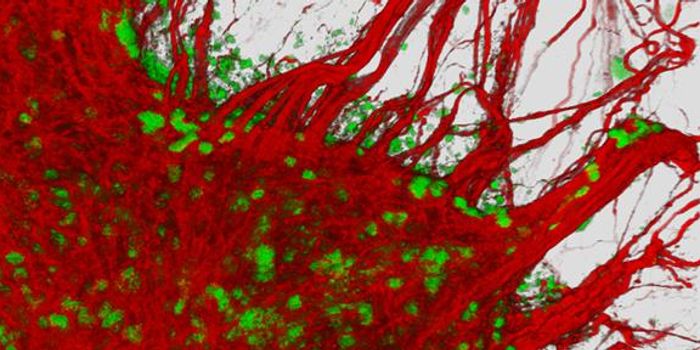

JUN 11, 2016MicrobiologyResearchers at the University of California, Riverside, figured out how Toxoplasma gondii causes neurodegenerative disea ...